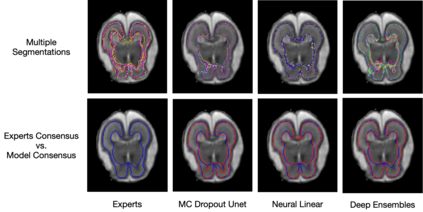

Medical imaging, including MRI, CT, and Ultrasound, plays a vital role in clinical decisions. Accurate segmentation is essential to measure the structure of interest from the image. However, manual segmentation is highly operator-dependent, which leads to high inter and intra-variability of quantitative measurements. In this paper, we explore the feasibility that Bayesian predictive distribution parameterized by deep neural networks can capture the clinicians' inter-intra variability. By exploring and analyzing recently emerged approximate inference schemes, we evaluate whether approximate Bayesian deep learning with the posterior over segmentations can learn inter-intra rater variability both in segmentation and clinical measurements. The experiments are performed with two different imaging modalities: MRI and ultrasound. We empirically demonstrated that Bayesian predictive distribution parameterized by deep neural networks could approximate the clinicians' inter-intra variability. We show a new perspective in analyzing medical images quantitatively by providing clinical measurement uncertainty.